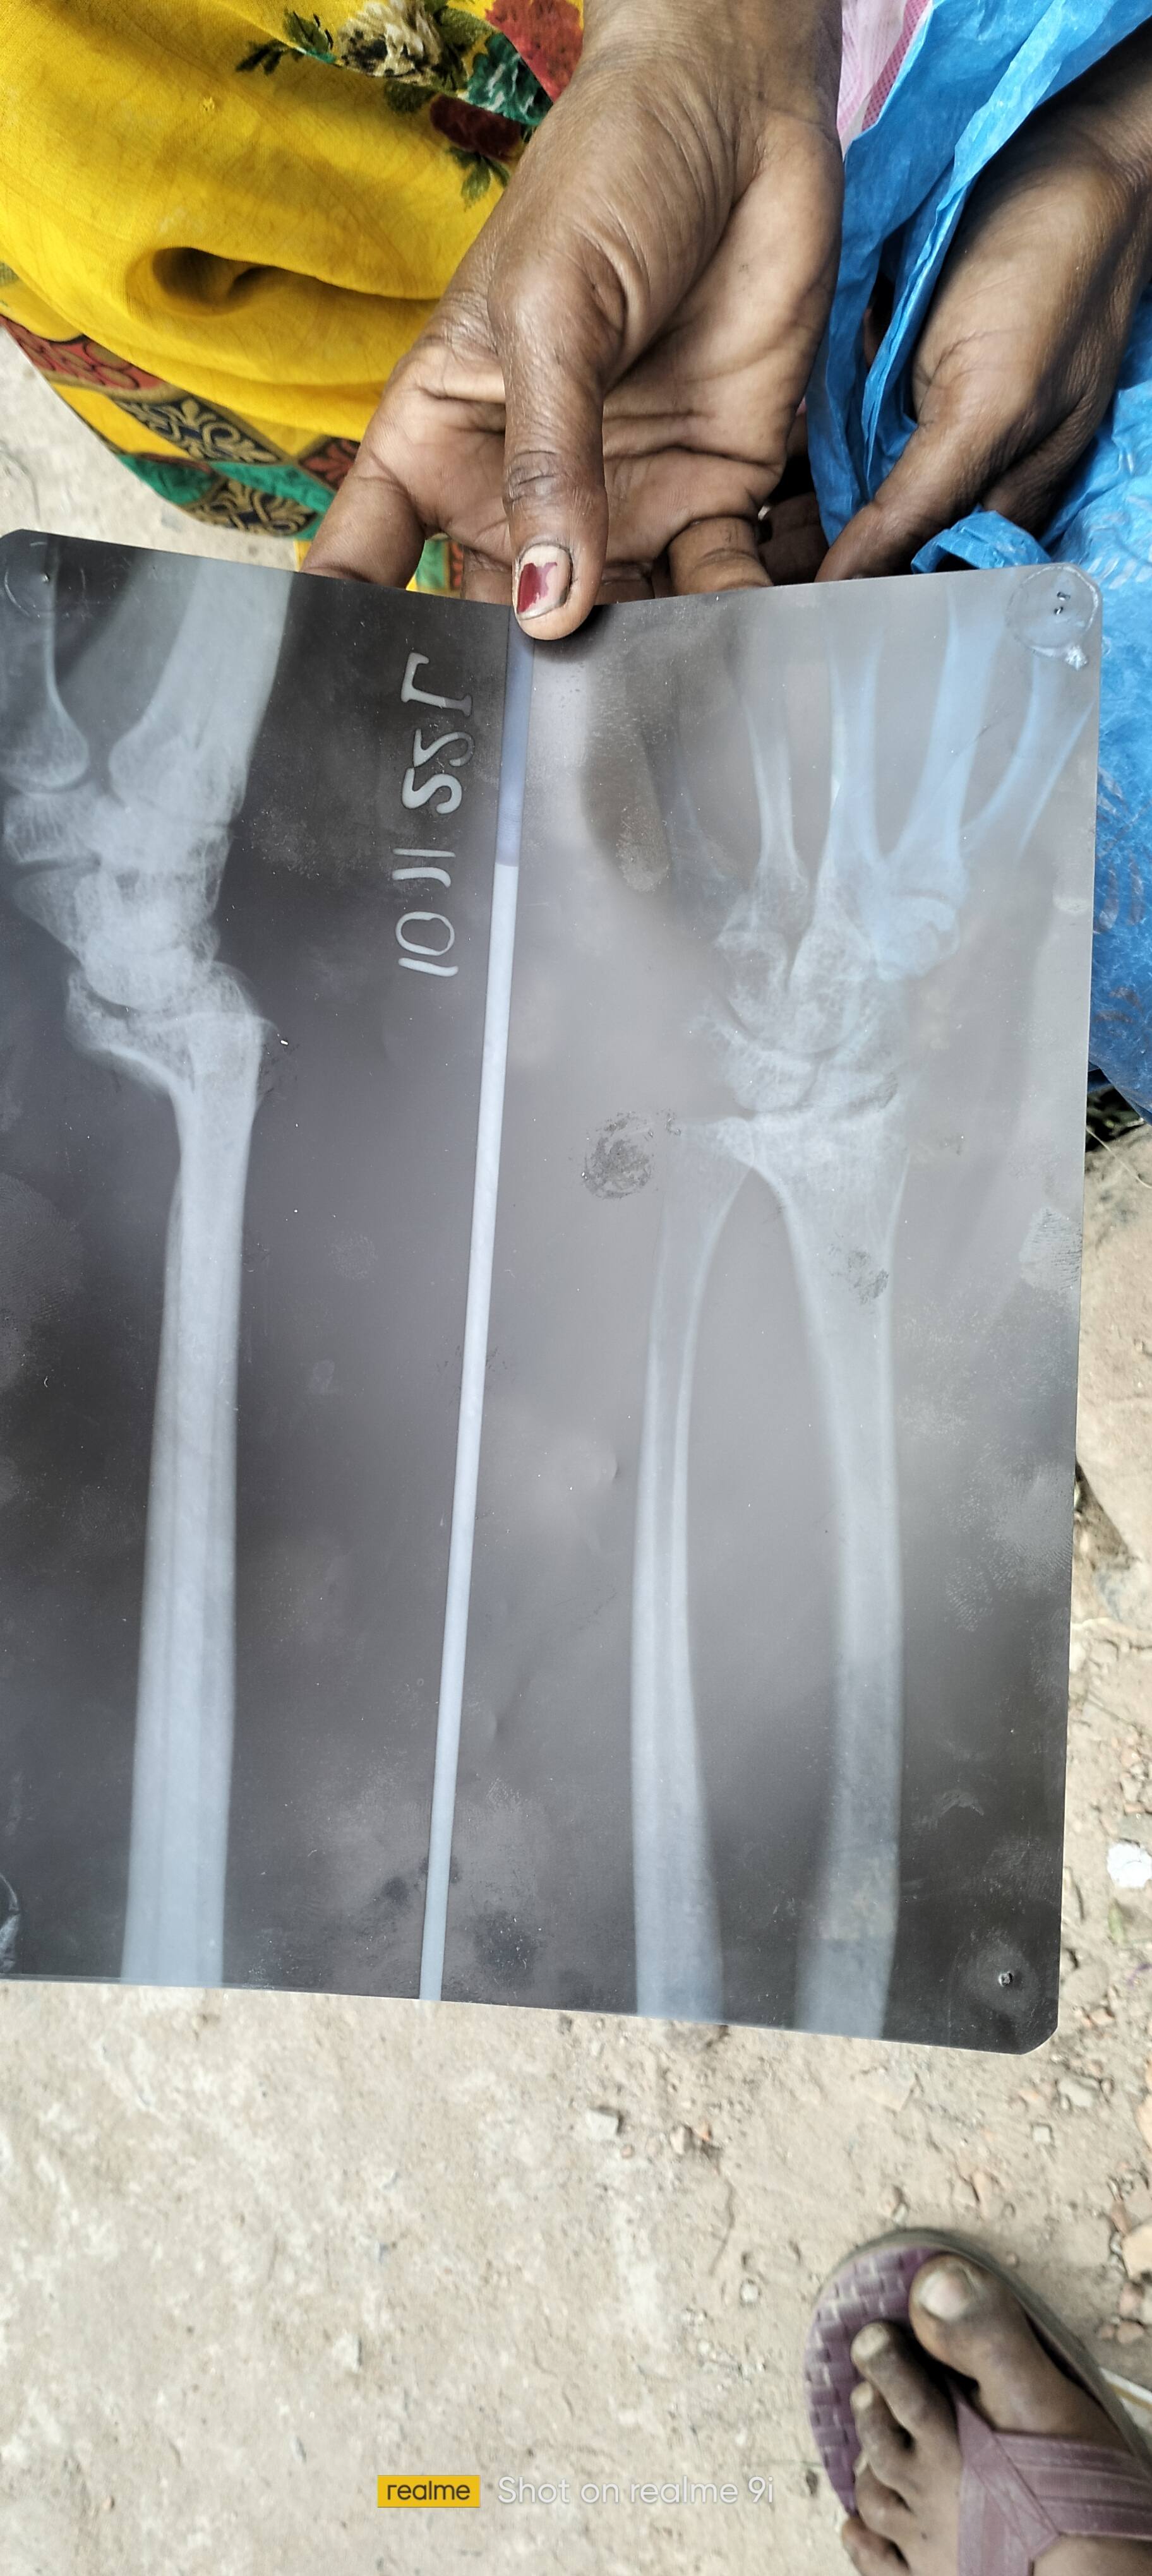

Mera plaster khul gay hai khulne ke bad hath tedha ho gya hai hath moment nahi kar raha hai Hadi jur gaya hai

...Read More